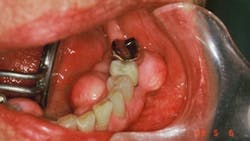

This unique loss of tooth structure (noncarious lesions, NCLs) has been the subject of controversy among dentists for almost 100 years (figure 1). W I Ferrier (1931) once remarked, “Their etiology seems to be shrouded in mystery.”8 We now understand that these multishaped deformations are examples of hard tissue fatigue due to compression failure. Fatigue, a weakened state brought about by repeated stressing, is one of the most insidious causes of loss of strength in a structure.9

Fatigue factors did not come into recognition until the introduction of rotating metal machinery in the middle of the nineteenth century. In time with the emerging science of biomechanics, dentists began to recognize their significance in the study of the mechanical behavior of living materials.10 Minute particles of tooth structure are being shed at vulnerable sites of high stress. The cuspid in figure 1 demonstrates changing sites of failure as alveolar bone recedes.